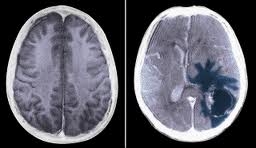

Manželka , Mamka - je po ťažkej operácii tumoru v hlave , operáciu podstúpila v Prahe , nakoľko bol tumor uložený vo veľmi ťažko prístupnom a životu ohrozujúcom priestore . Napriek úspešnej operácii niekedy stráca videnie a stabilitu . Invalidný manžel po troch operáciach chrbtice je bez možnosti zamestnať sa . Rodina sa dostáva do hlbokej krízy a ich tri deti potrebujú ešte pomoc .

Ale vráťme sa k tomu , prečo som túto výzvu napísal , vráťme sa o niekoľko mesiacov naspäť ........ keď manželke v máji diagnostikovali tumor v oblasti mozgovej artérie a očných nervov o veľkosti skoro 4x3x1,5 cm .... nechceli sme tomu uveriť , aj keď príznaky toho sa objavili už skôr . Človek si stále nepripúšťa to najhoršie a neverí , až keď sa nezačal kolotoč vyšetrení a konzultácií s neurológmi a neurochirurgom . Bála sa manželka a bál som sa aj ja , keď nám povedali že sa ten tumor nachádza v ťažko prístupnej oblasti a klasickou operáciou by mohlo dôjsť k devastačným poškodeniam mozgu , rozhodli sme sa pre operáciu Lekselovým Gama nožom v Prahe , nakoľko Slovensko nedisponuje takouto stereotaktickou technikou . Je to menej invazívna metóda , ale náročná na liečenie a rekonvalescenciu . Celková doba liečenia po týchto zákrokoch je 2 - až - 5 rokov . V celkovom sledovaní je pacient ďalších 5 rokov takže povedať že sme vyhrali môžme až po 10 - tich rokoch .